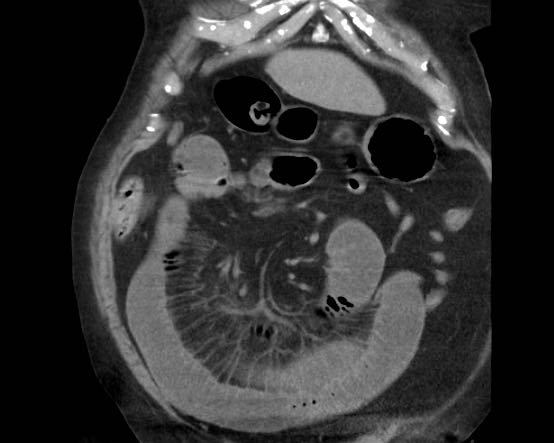

CT trong viêm túi mật cấp

CT có thể rất hữu ích trong các trường hợp siêu âm không cho kết quả chẩn đoán.

Đây là hình ảnh của một bệnh nhân béo phì với đau hạ sườn phải cấp tính trong 6 giờ. CRP 2.

Siêu âm cho thấy túi mật lớn có bùn mật, không quan sát thấy sỏi.

Việc ấn vào túi mật không đáng tin cậy do vị trí cao dưới cung sườn phải.

Không có bất thường siêu âm nào khác.

CT thực hiện cùng ngày cho thấy túi mật lớn với chỉ những thay đổi quanh túi mật kín đáo và không có nguyên nhân nào khác giải thích cho các triệu chứng.

Ngày hôm sau CRP là 105 và CT không tiêm thuốc cản quang lặp lại cho thấy quầng mờ xung quanh túi mật.

Phẫu thuật tiếp theo xác nhận viêm túi mật cấp giai đoạn sớm do sỏi nhỏ trong ống túi mật.